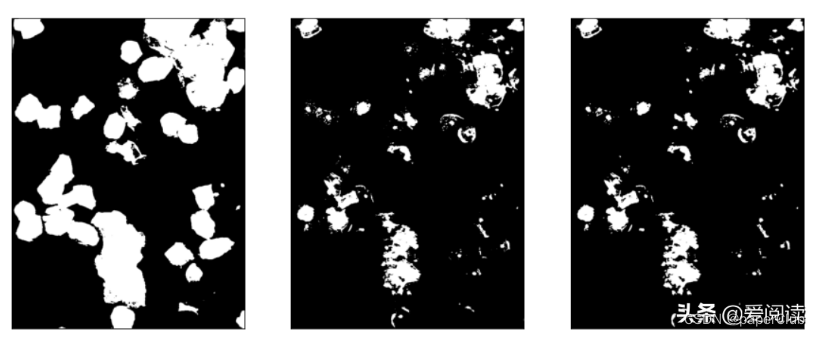

plt.subplot(131), plt.imshow(bw_cell, 'gray'), plt.xticks([]), plt.yticks([])

plt.subplot(132), plt.imshow(bw_cell1, 'gray'), plt.xticks([]), plt.yticks([])

plt.subplot(133), plt.imshow(bw_cell2, 'gray'), plt.xticks([]), plt.yticks([])

细胞区域初步分割结果: